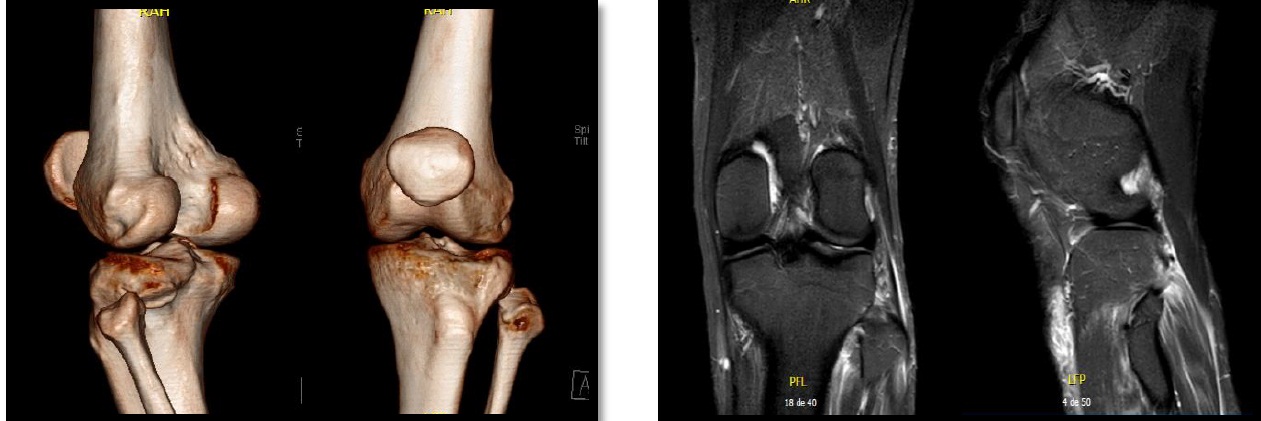

Luxación traumática aguda de la articulación tibioperonea proximal. Reporte de un caso y revisión bibliográfica. [Acute traumatic dislocation of the proximal tibiofibular joint: case report and review of the literature].